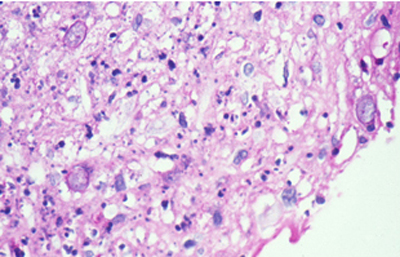

Cuando el examen patológico se realiza en cortes de tejido corneal procesados en parafina, (biopsias y discos de córnea de queratoplastias) las coloraciones que empleamos usualmente son la coloración de Hematoxilina-Eosina (Figura 49), el Blanco de Calcofluor. (Figura 50), la de PAS (Figura 51 y 52). De nuevo, la consideración de que una infección corneal puede ser causada por Acantamoebas es la condición indispensable en el diagnóstico diferencial para llegar a su diagnóstico

Fig. 49 H-E, Original x160